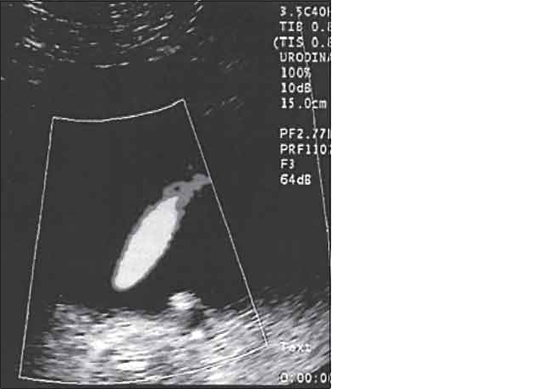

Доплерограма

На малюнку помітно зниження функції нирок виявляється ненасичений інтраренального малюнка, зниження по часу або мінімальної швидкості кровотоку. Всі ці критерії характеризуються патологією і потребують оперативного втручання.

Сканування лівого сечівника через сечовий міхур. На доплерограмах чітко видно криву ретроградногопотіку сечі. Швидкість потіку 0,52m/s, Час 1,16s)

Сканування лівого сечівника через сечовий міхур. На доплерограмах чітко видно криву ретроградногопотіку сечі. Швидкість потіку 0,22m/s, Час 2,38s)

На доплерограмі сечоводів СМР 2,3 і4 ступені спостерігається: делятація сечівника в нижніх і верхніх відділах при середньому або максимальному наповнені сечового міхура, циклічні зиіни діаметра сечівника в нижніх і верхніх відділах: доплерографічна регістрація зворотнього току сечі в сечоводі:стабільне розширення миски: зменшення розмірів нирки.